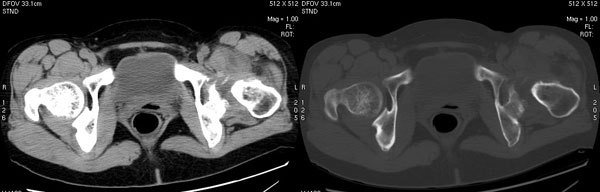

以下是引用jiajie在2006-7-14 17:19:00的发言:[br]ct所见:双侧髋关节不对称,左侧关节间隙变窄,关节面毛糙。左侧股骨头变形、无明显变小,前上缘与髋臼融合,融合处骨质明显增生硬化,并见数个小囊变影。股骨头下端与股骨颈交界部见囊样变,邻近肌肉内见囊样密度减低区,ct值24hu。右侧髋关节形态未见异常。[br][br]ct诊断:左侧髋关节结核可能,请结合临床资料进一步分析。

以下是引用lihuuuu在2006-12-5 10:14:00的发言:[br]定位像示:左侧髋臼变浅,倾斜度加大,髋臼外上缘呈波浪状不规则,骨质增生硬化,髋关节上缘间隙明显变窄,股骨头向外上轻度移位。轴位像示:左侧股骨头变形,前上缘与髋臼融合,融合处骨质明显增生硬化,并见数个小囊变影。股骨头下端与股骨颈交界部见囊样变,邻近肌肉内见密度减低区,ct值24hu,内缘见弧形高密度钙化影。右侧髋关节形态未见异常。[br]ct诊断:左侧髋臼发育不良[br] 左侧股骨头缺血性坏死[br] 左侧肌肉内低密度影伴有高密度钙化-考虑早期骨化性肌炎[br] [br]“我认为在描述上已经写了肌肉部分,印象诊断里应该写主见”[br]